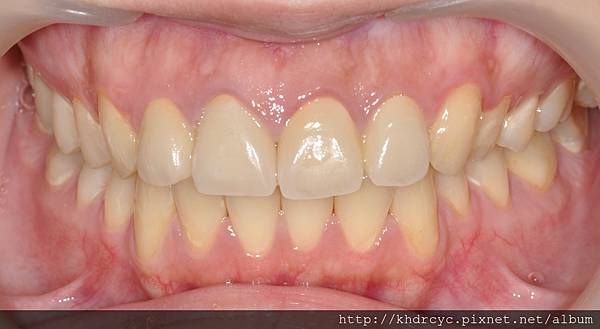

配合療程仁武的C小姐裝上全瓷假牙套

美觀立刻得到改善

等待門面牙肉與全瓷假牙貼合的過程

仁武的C小姐最訝異的

是美觀能改變這麼多

且在這麼短的時間內就發生